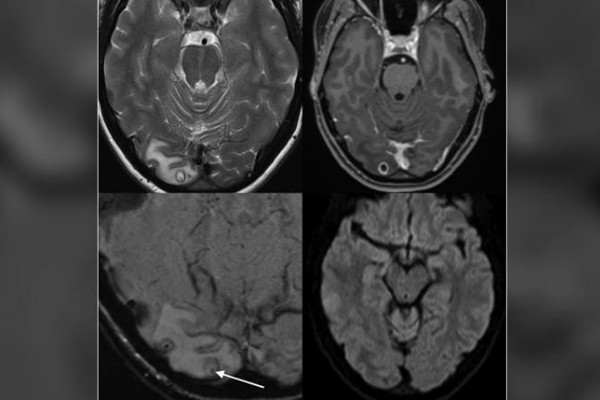

Hình ảnh nang sán làm tổ trong não khiến bác sĩ nhầm tưởng là khối u

Gần đây cô bị đau đầu dữ dội trong suốt hơn 1 tuần kèm giảm thị lực. Kết quả chụp MRI sọ não tại bệnh viện phát hiện có khối u trong não, bác sĩ nghi ngờ đây là căn nguyên gây ra các cơn đau đầu.

Tuy nhiên khi phẫu thuật lấy u, bác sĩ phát hiện bên trong chứa đầy nang sán dây lợn. Ấu trùng sán lợn khi xâm nhập vào hệ thần kinh có thể đau đầu, mù lòa, viêm màng não, mất trí nhớ, co giật, động kinh, thậm chí tử vong nếu không được phát hiện kịp thời.